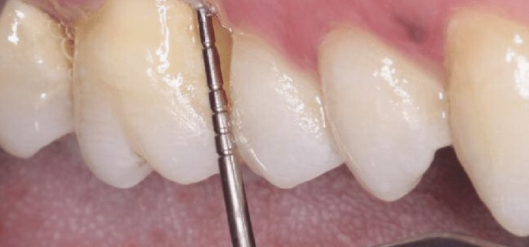

눈금이 표시되어있죠~?

잇몸 깊이를 재는 도구를 사용하여

잇몸을 재보았는데

쑤욱 들어갑니다.

아 이건 별로 좋지 않은 시그널인데요.

탄탄한 잇몸은

안들어가야하거든요